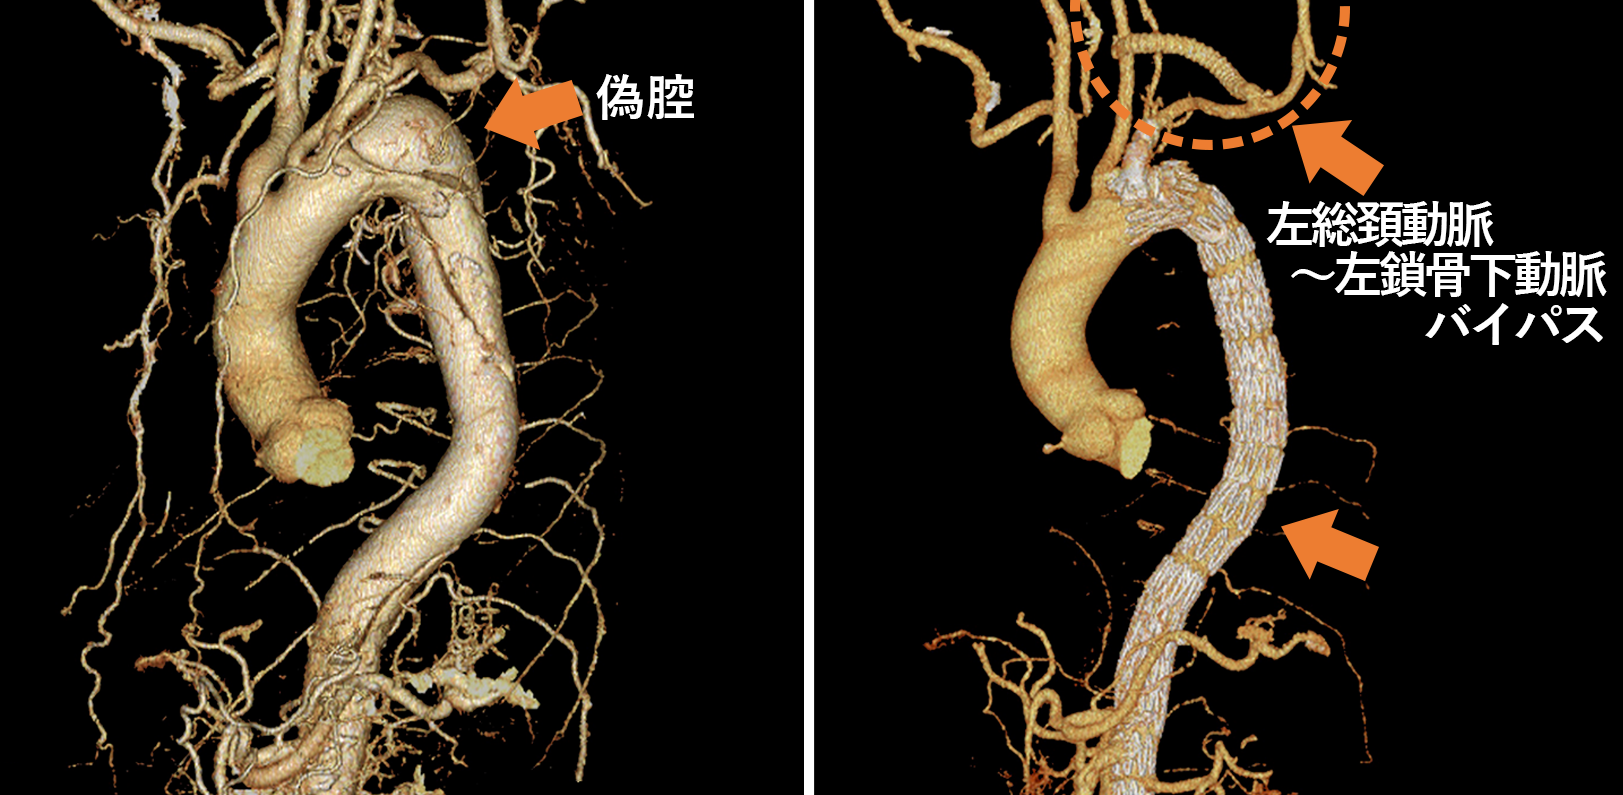

・開胸人工血管置換術、胸部ステントグラフト内挿術を患者様に応じて使い分けて治療を行っています。

・大動脈解離や弓部大動脈瘤ではフローズンエレファントトランクを積極的に活用して手術時間の短縮に努めています。

・ステントグラフトでZONE2からの1-Debranch TEVARが難しい症例はPhysician-Modified Stent GraftでZONE0から治療しています。

・B型解離で今後瘤拡大のリスクが高い患者様にPreemptive TEVARを行っています。